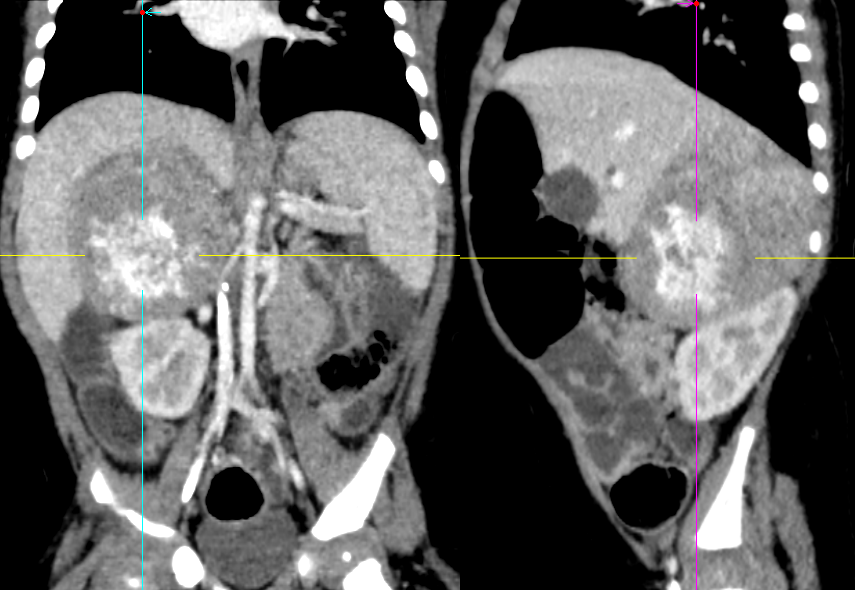

神经母细胞瘤 CT 表现:腹膜后边缘清楚大肿块;瘤内可见粗大、无定型或斑点状的钙化,增 强扫描不均匀明显强化。肿块较大,最大径 6-8 cm,形态不规则,边缘呈分叶状,有薄层包膜或无包膜;大部分呈 T1WI 低至中等信号、T2WI 中高信号;增强扫描实性部分明显强化。